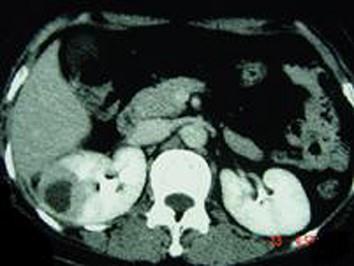

问题 女,12岁,右腰部疼痛10天,尿检可见大量的脓细胞 CT平扫+增强如图所示,应诊断为 ( )

选项 A、右侧肾癌 B、右肾结核 C、右侧感染性肾囊肿 D、右肾转移瘤 E、右肾脓肿

答案 E